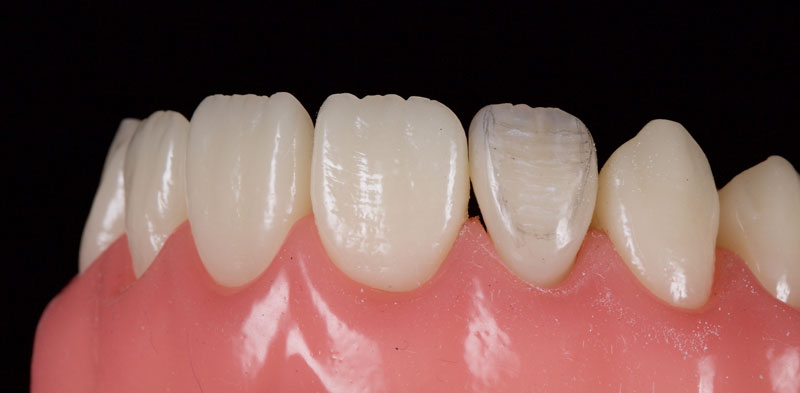

- Single Tooth: This is a microdontia localized to one tooth. Most peg laterals seen in a general dental practice setting will be of this type. See Fig. 3 (pre-op) and Fig. 4 (immediate post-op treated with direct resin).

- Treatment planning: The assessment can be done simply via clinical examination, though study casts/scans may be employed if they are available. The peg lateral should be observed from the occlusal aspect (Fig. 5).

Ideally, the tooth should be in the center of the space mesio-distally, so the mesial and distal gingival emergence profiles are optimized. Furthermore, the incisal-facial portion of the tooth must be around 1 mm palatal to the adjacent canine and central incisor — that is, the peg lateral needs to be slightly palatally placed.

In my experience, the most common reason for the peg lateral restoration’s restorative failure is inadequate restorative space, which results in a bulky buccally placed veneer.